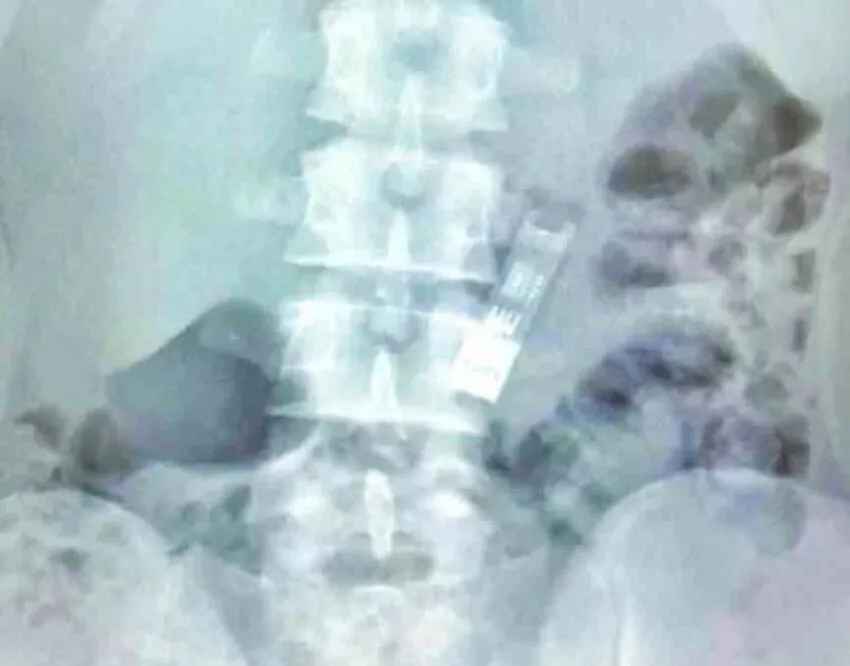

Врачи Детского клинического центра имени Л.М. Рошаля успешно извлекли из желудка 16-летнего школьника флеш-накопитель, содержащий его домашнее задание по информатике.

Инцидент произошел, когда мальчик, выполнив задание, случайно проглотил флешку во время игры. После безуспешных попыток дождаться естественного выхода инородного тела, семья обратилась за медицинской помощью.

"Непредвиденный случай с домашним заданием по информатике произошел с 16-летним мальчиком, который обратился в Детский клинический центр имени Л. М. Рошаля. Он выполнил свою работу и загрузил ее на флешку, после чего решил поиграть и начал крутить флешку перед лицом. Однако в какой-то момент он случайно проглотил ее", - рассказали в пресс-службе министерства.

Благодаря оперативным действиям врачей, флешка была извлечена без вреда для здоровья подростка. Уже на следующий день мальчик был выписан из больницы.

Примечательно, что флешка сохранила работоспособность, и школьник успешно сдал домашнее задание по информатике.